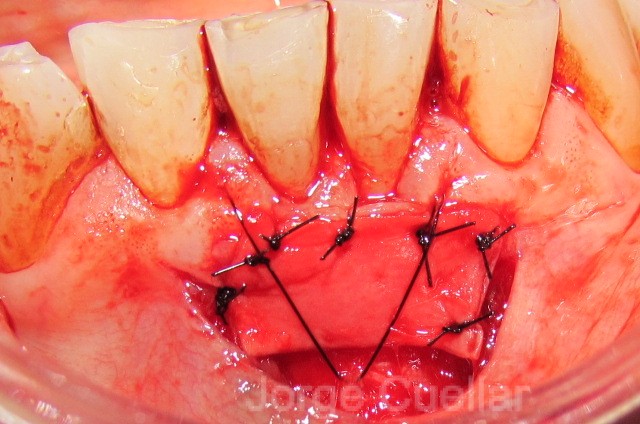

In this case, because the patient now has good oral hygiene in the affected region, the recession is unlikely to proceed significantly and could be monitored, so graft placement is a viable. The recipient area was prepared with a split thickness flap which was fixed apical with periosteal sutures. Free gingival harvest free gingival graft.

Taking her own tissue from the roof of her mouth to sites #22 and 27 (bottom front). This is a versatile procedure and can also be used over an extraction socket or osseous graft 32, 33. Esthetic free gingival graft pamela nicoara dds esthetic free gingival graft no vertical release, no scars graft survives from blood supply from periosteum, bone and overlying flap would suture w/ 6.0 gut esthetic, predictable, and stable over time 56y/o male w/ hiv for 20 years enamel flaking (impossible to get graft onto enamel), needs new restoration … didn’t think about root coverage.